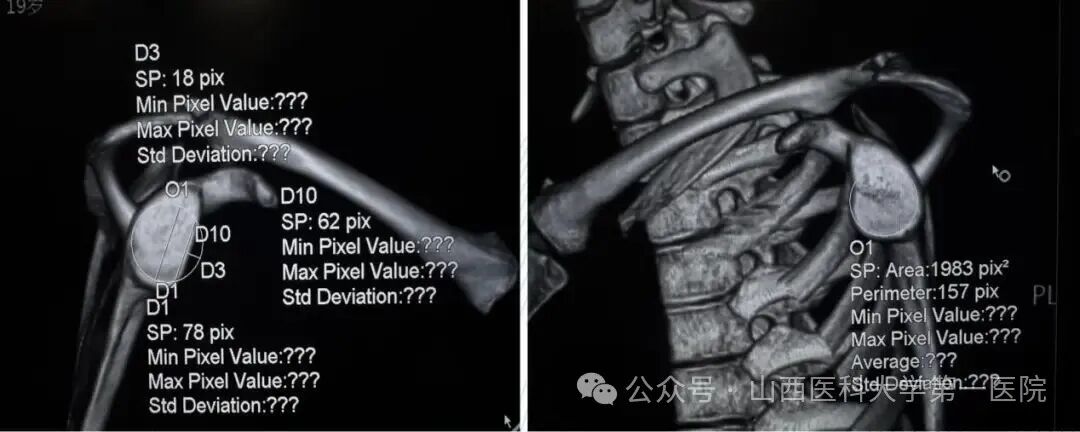

术前,患侧肩关节盂与健侧相比,缺损约25%

术后CT三维重建:关节盂前下完美覆盖